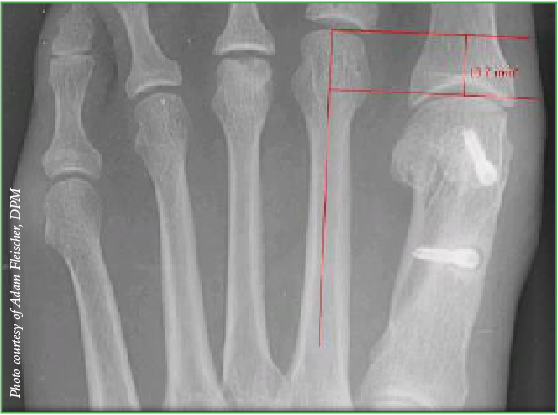

Poster co-author Adam Fleischer, DPM, notes that more than a 4 mm difference in length between the first and second metatarsals on AP radiographs may suggest that a shortening metatarsal osteotomy of the second metatarsal, such as a Weil or other osteotomy, is indicated during second MPJ plantar plate surgery.

Dr. Fleischer and colleagues have found the most effective method for measuring the metatarsal parabola as it pertains to plantar plate pathology is Nilsonne’s method (see above X-ray). He acknowledges the limitation that this method may not work as well for patients with large intermetatarsal angles and the study’s findings may not be generalizable to all patients with various foot sizes. The average patient in the study was a 55-year-old female with a size 7 shoe, notes Dr. Fleischer, who is affiliated with the Weil Foot and Ankle Institute in Des Plaines, Ill. and is an Associate Professor of Radiology and Medicine at the Dr. William M. Scholl College of Podiatric Medicine.